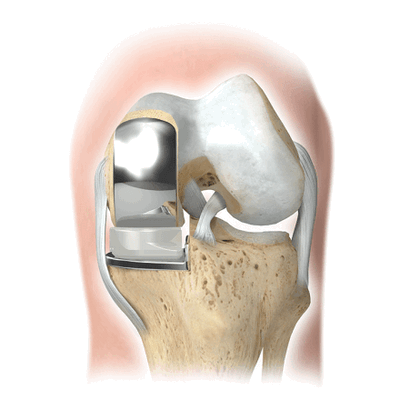

Если сустав поражен указанным на изображении образом, то возможна его частичная замена.

Основной метод лечения - постановка эндопротеза вместо поврежденного сустава. Раньше выполнялось преимущественно тотальное эндопротезирование коленного сустава, однако сейчас активно развивается другое направление - одномыщелковое (частичное) эндопротезирование.

Одномыщелковые — частичные эндопротезы

Направление эндопротезирования длительное временя активно развивалось. Сейчас современные протезы соответствуют всем базовым требованиям. Они способны стать полноценной заменой коленному суставу.

Как это выглядит после операции.